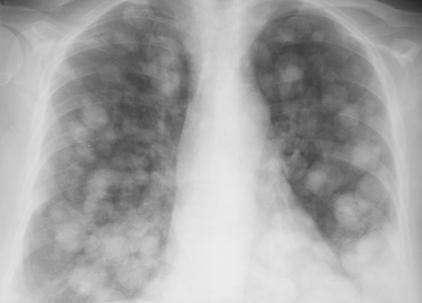

Fig. 24 – Metastaze pulmonare (opacitati nodulare si macronodulare multiple, diseminate pe ambele arii pulmonare, omogene, de intensitate medie, imprecis delimitate)

Din punct de vedere radiologic intalnim 3 forme:

- opacitati rotunde unice (metastaze solitare) situate in bazele pulmonilor;

- opacitati micronodulare pe toata aria pulmonara, ce apar in diseminarile hematogene;

- limfangita carcinomatoasa, caracterizata prin edem interstitial cu trabeculatii hilifuge si linii Kerley.